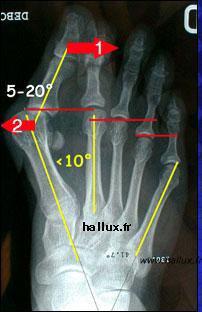

Le gros orteil se déplace vers les autres (1), tandis que le premier métatarsien (os situé à la base du gros orteil) se dirige dans les sens opposé (2). Cet angle forme une"bosse" qui n'est pas de l'os supplémentaire. L'opération devra corriger cet angle pour supprimer cette saillie. Les tendons prennent la "corde de l'arc" et accentuent encore cette déformation.

Le gros orteil (hallux) se déplace en dehors (1)

tandis que le premier métatarsien se déplace vers l'intérieur (2)

Il en résulte un angle qui correspond à la "bosse" que l'on observe.

Le traitement chirurgical consiste à redresser ces éléments...